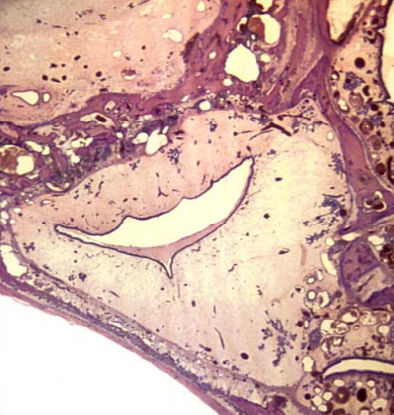

)__ cartilage is in this tracheal ring

hyaline

this is a slide of the ___

larynx

this is ___ cartilage

cricoid cartilage (from larynx slide)